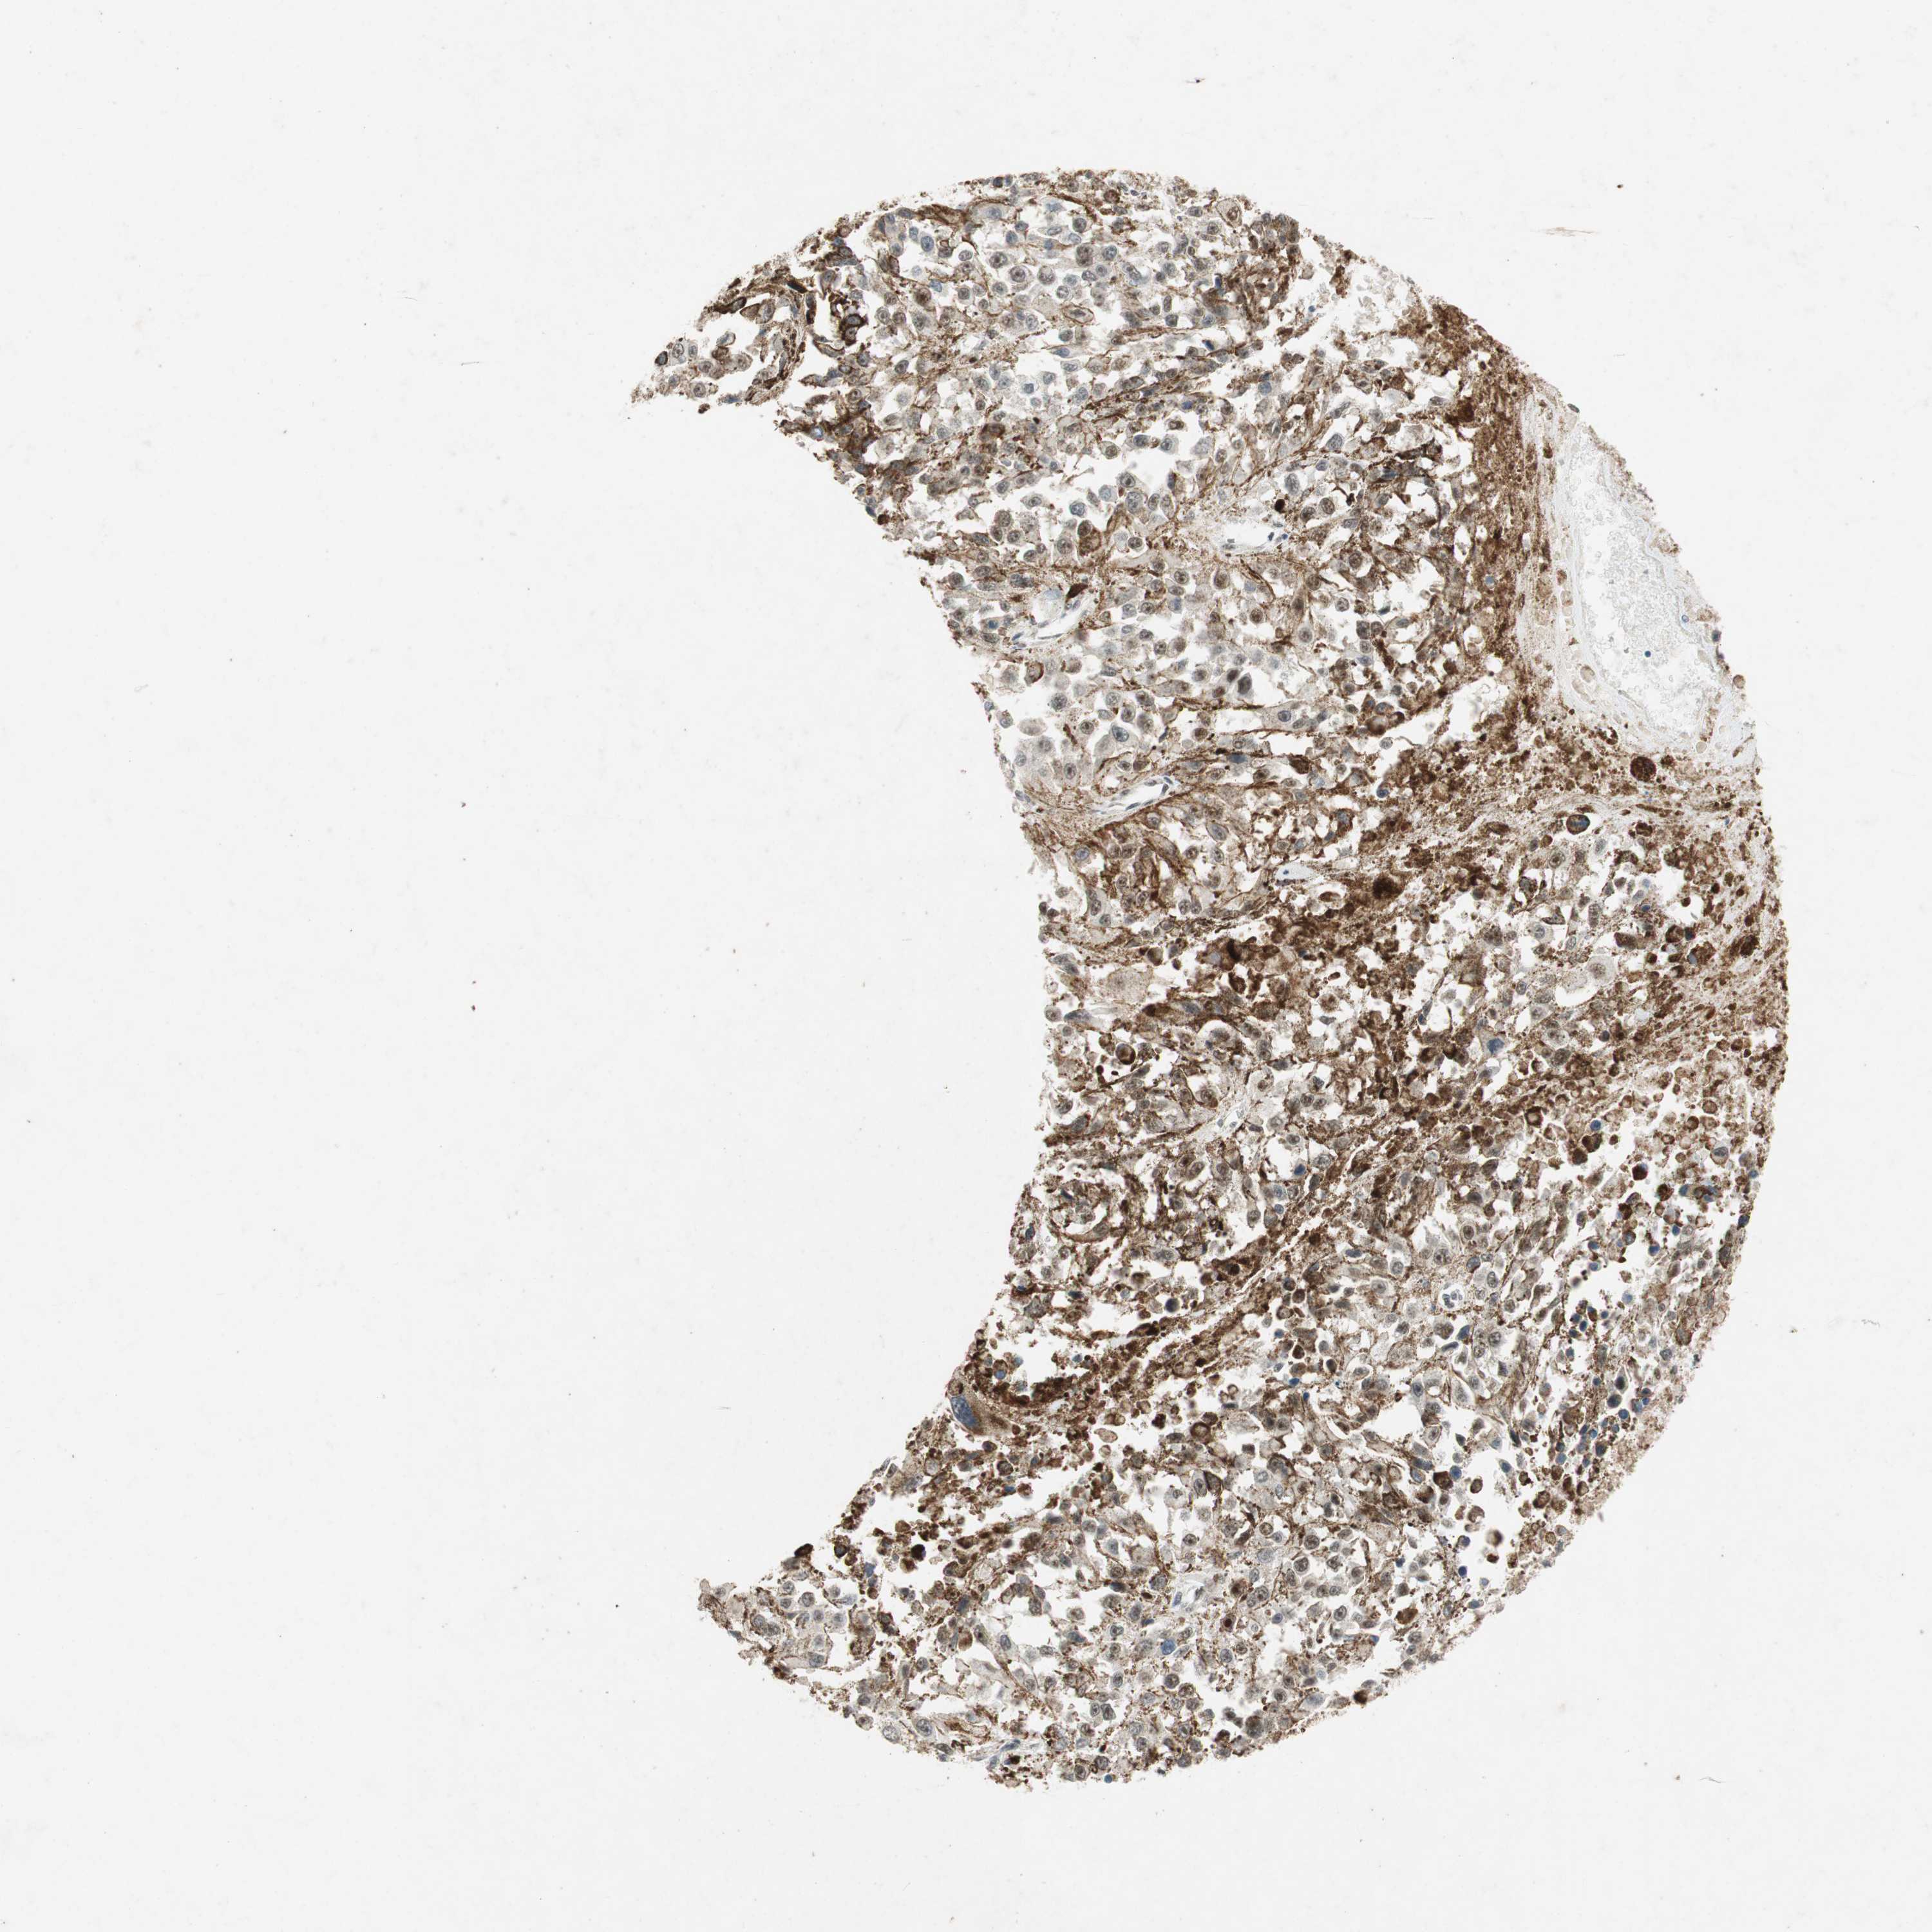

MELANOMA - Protein expressioni

A mouse-over function shows sample information and annotation data. Click on an image to view it in a full screen mode. Samples can be filtered based on level of antibody staining by selecting one or several of the following categories: high, medium, low and not detected. The assay and annotation is described here.

Note that samples used for immunohistochemistry by the Human Protein Atlas do not correspond to samples in the TCGA dataset.

Antibody stainingi

Antibody staining in the annotated cell types in the current human tissue is reported as not detected, low, medium, or high, based on conventional immunohistochemistry profiling in selected tissues. This score is based on the combination of the staining intensity and fraction of stained cells.

Each image is clickable and will lead to virtual microscopy that enables deeper exploration of all samples and also displays staining intensity scores, fraction scores and subcellular localization as well as patient and tissue information for each sample.

Antibody HPA008959

Antibody HPA013195

Location

Nuclear

Cytoplasmic/membranous

Cytoplasmic/membranous,nuclear

None

Malignant melanoma, NOS

Malignant melanoma, Metastatic site